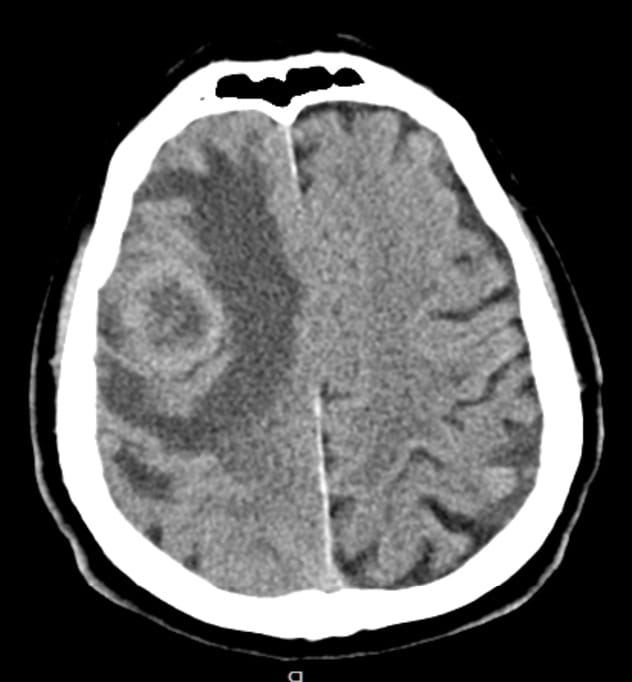

Traumatic Intracranial Hypertension NEJM Differential Intracranial Hypertension Intracranial hypertension (ih) is a clinical condition that is associated with an elevation of the pressures within the cranium. Symptoms often include severe headaches, blurred vision, blind. Intracranial hypertension can put pressure on your optic nerve. Idiopathic intracranial hypertension is a condition of raised intracranial pressure of unknown cause. Idiopathic intracranial hypertension (iih) is a disorder of unknown etiology that. Differential Intracranial Hypertension.